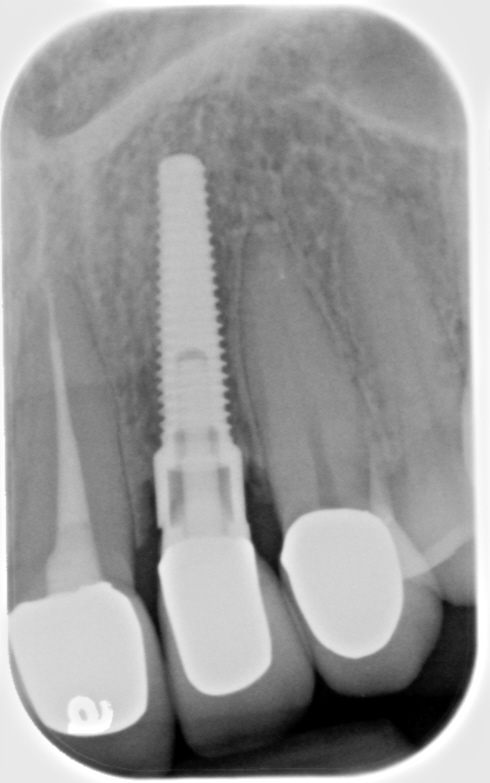

Fig 8. Loss of restoration and subsequent tissue overgrowth from broken abutment screw as shown in the radiograph (Fig 9).

Figure 8

Fig 9. Radiograph depicting fractured screw inside of the implant.

Figure 9